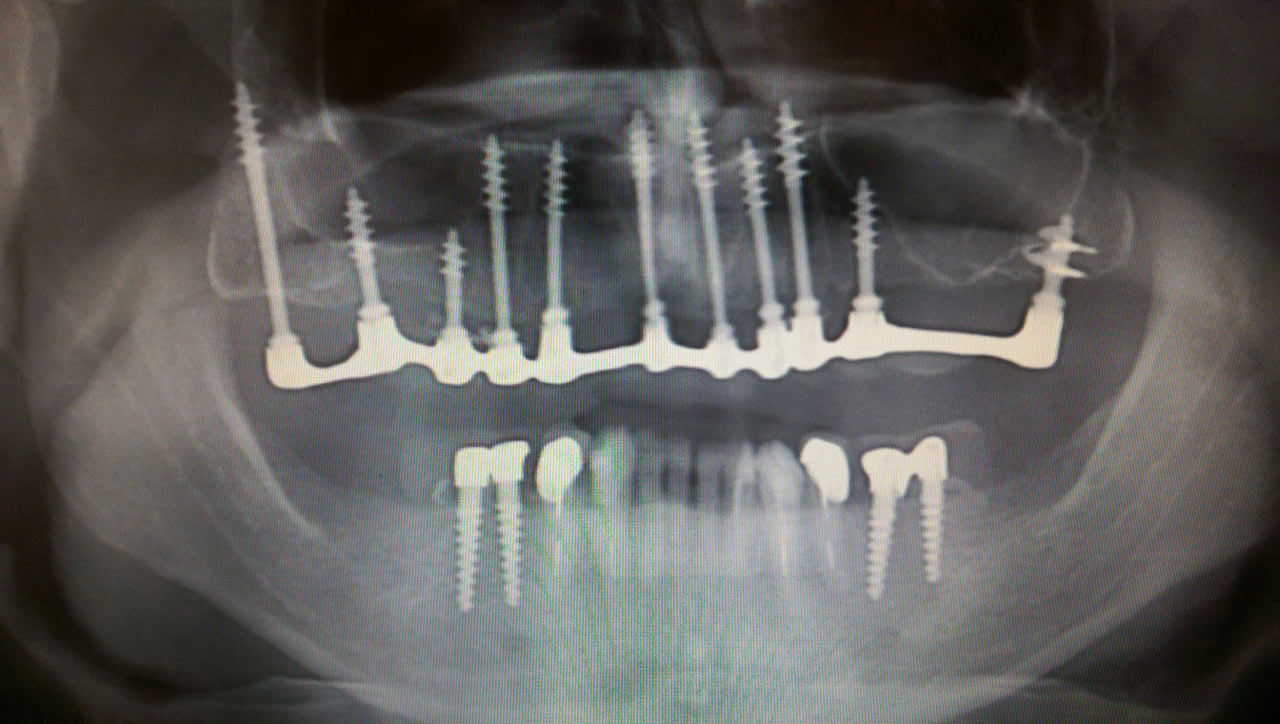

Elhanyagolt fogsor cseréje 2 nap alatt

2 nap alatt varázsoltuk ezt a szép esztétikus alsó, felső körhídat implantátumokkal megtámasztva a korábban elhanyagolt szájba. Az 1. nap 26 fogat távolítottunk el, mert annyira rossz állapotban voltak, és rögtön azonnal terhelhető IHDE svájci implantátumokat raktunk be, fentre 8, lentre 6 darabot. A sebeket összevarrtuk és intraorális szkennerrel digitális lenyomatot vettünk. 2 nap múlva pedig beragasztottuk a kész PMMA műanyag körhidakat. Dr. Kelemen Péter és a Symbion Fogtechnika munkája.